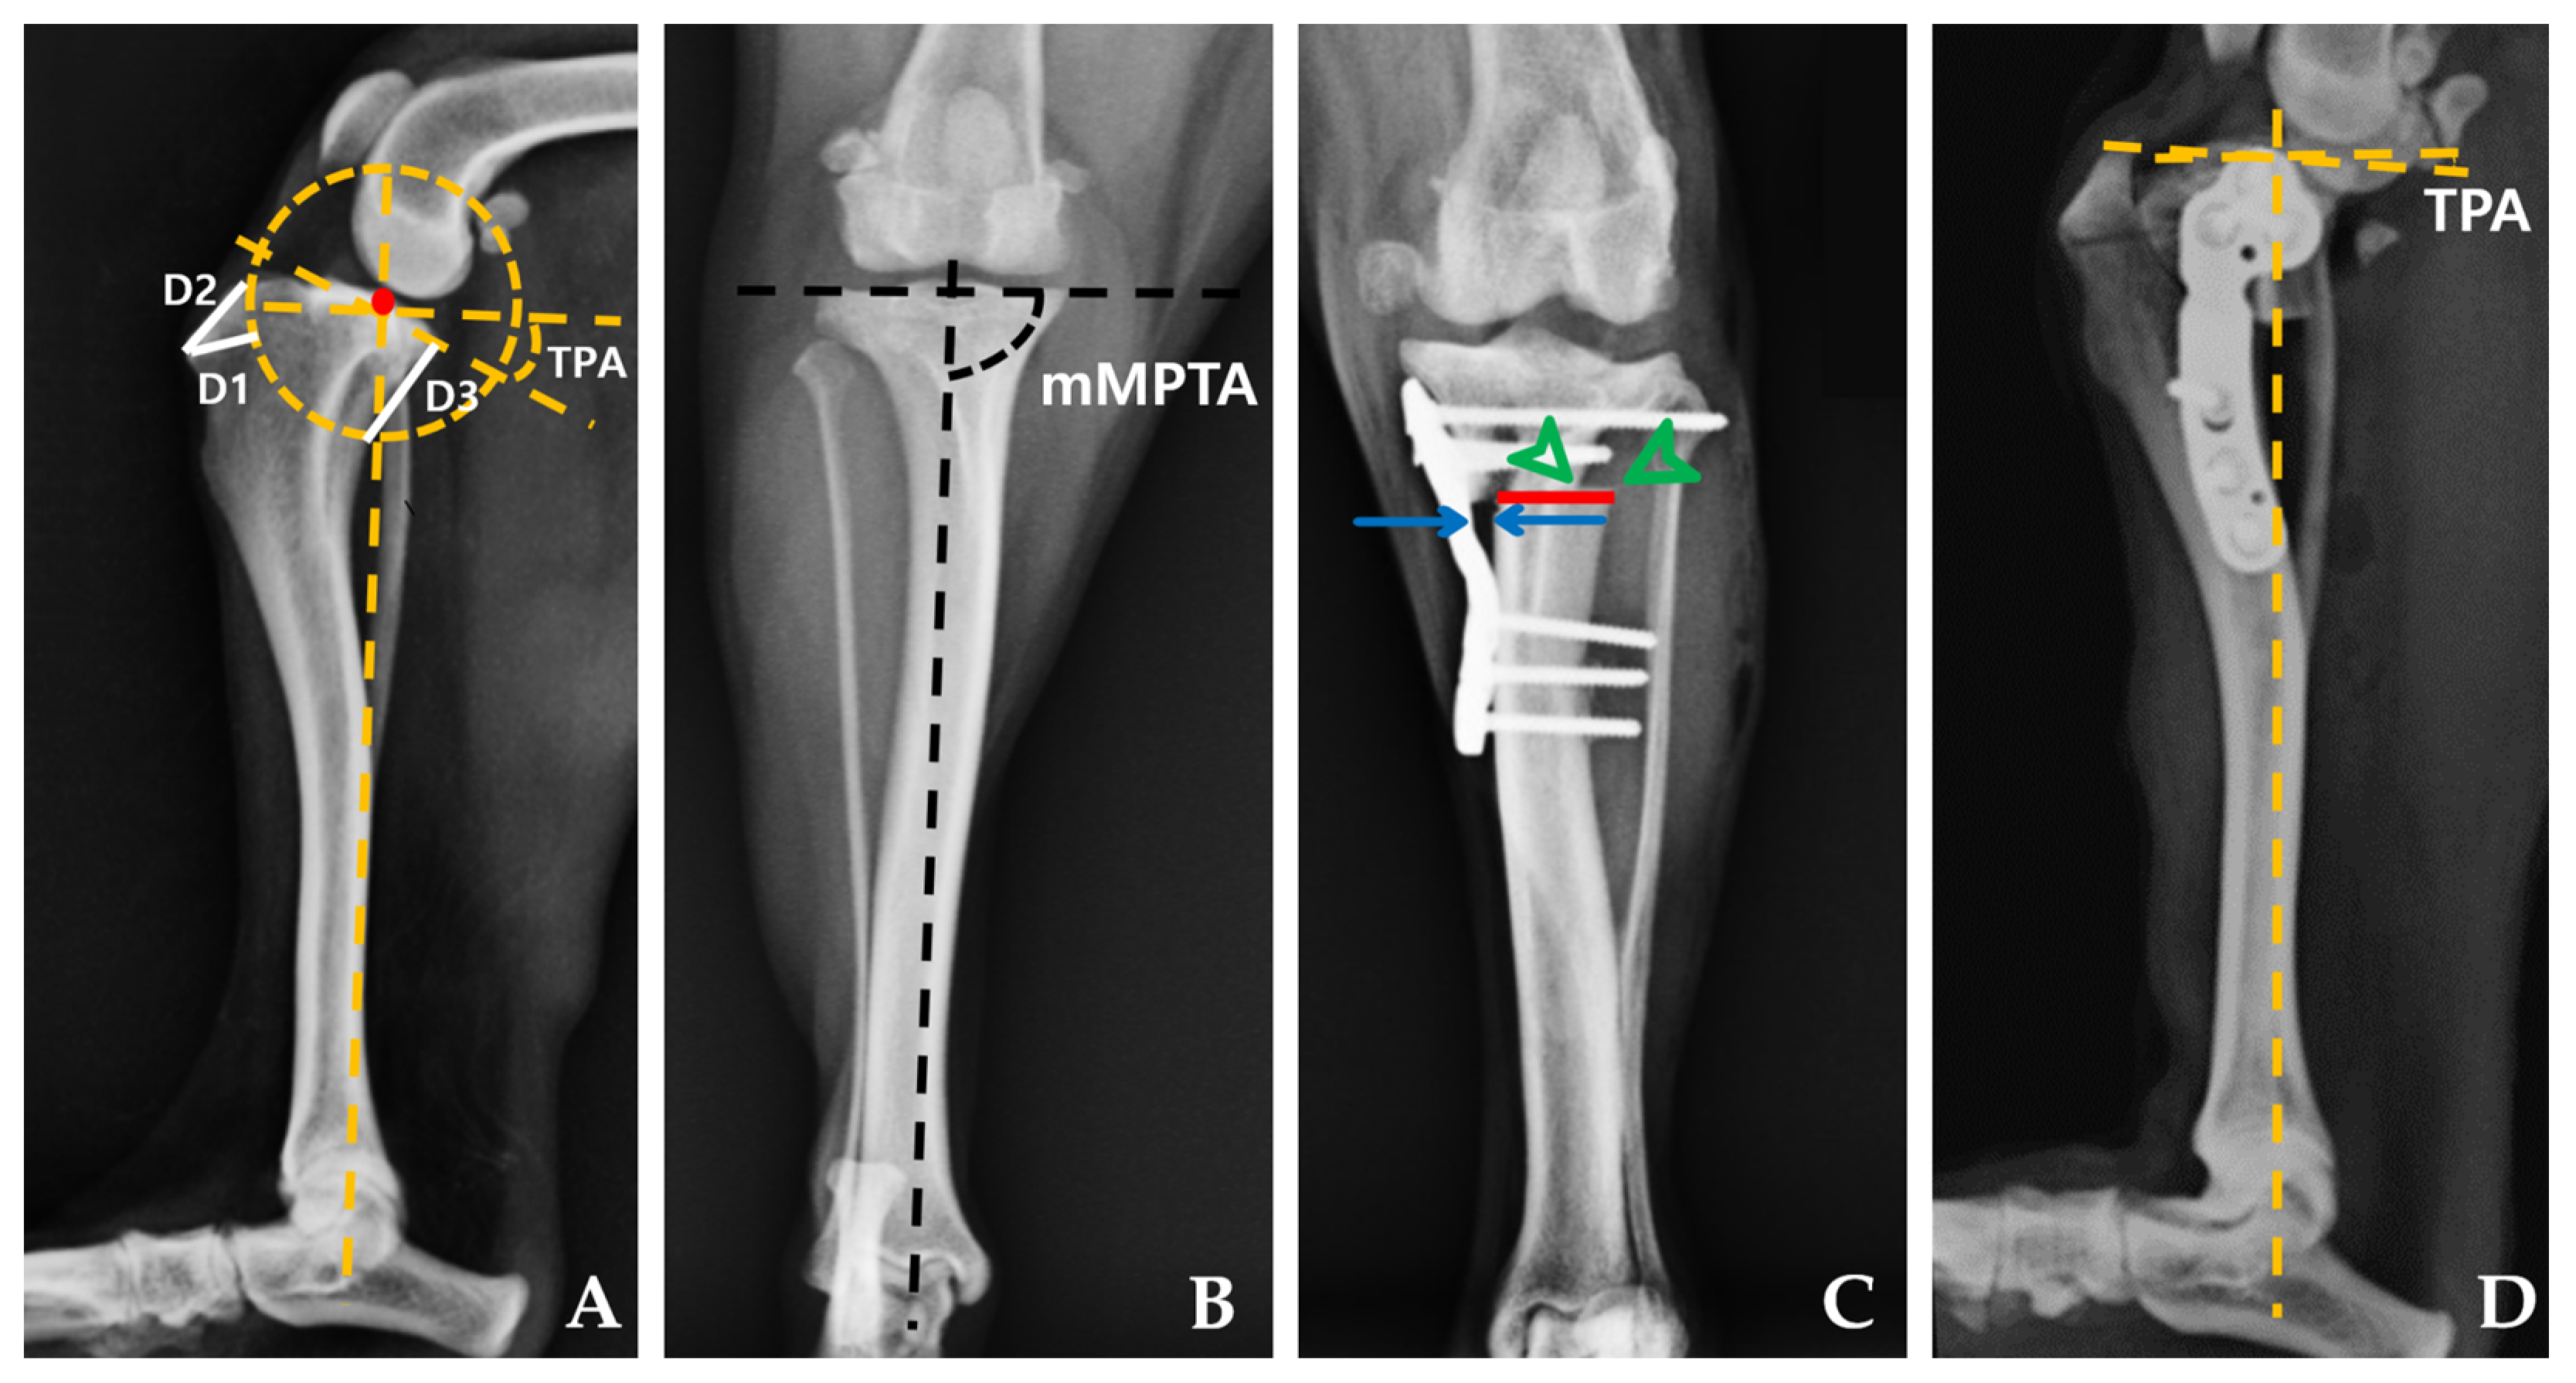

2.4.1. Radiographic Measurements

| Preoperative TPA (°) | 25.00 | 2.00 | 25.25 | 2.86 | 0.798 |

| Postoperative TPA (°) | 5.48 | 1.66 | 5.38 | 2.15 | 0.878 |

| Preoperative mMPTA (°) | 96.96 | 4.33 | 96.13 | 6.17 | 0.721 |

| Postoperative mMPTA (°) | 97.04 | 1.84 | 94.34 | 4.38 | 0.131 |

| Bone–plate gap (mm) | 0.59 | 0.54 | 1.90 | 0.44 | 0.001 |